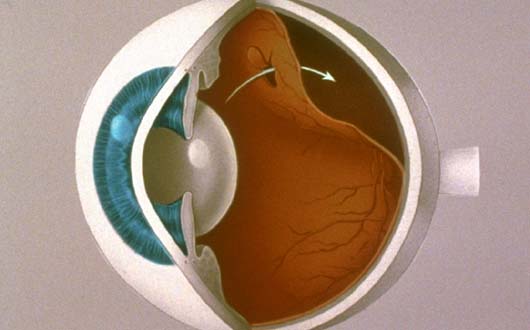

Retina